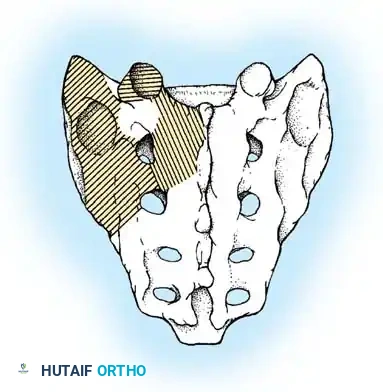

The Hall Technique

The Hall technique offers an alternative method for facet obliteration and grafting, particularly useful in rigid deformities.

Fig. 38-28: The Hall technique of facet fusion, involving sharp excision of the inferior facet and trough creation.

- Sharply amputate the inferior articular facet with a gouge and remove the bone fragment entirely. This exposes the cartilage of the superior facet.

- Remove the exposed cartilage completely with a sharp curet.

- Create a bleeding trough by removing the outer cortex of the superior facet.

- Impact cancellous bone grafts directly into this vascularized trough.

- Complete the procedure with global decortication of the posterior elements.